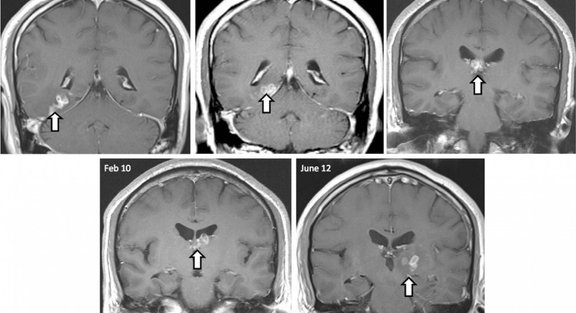

В течение нескольких лет томографы показывали, как странный участок перемещается по мозгу, и в итоге врачи решились на операцию.